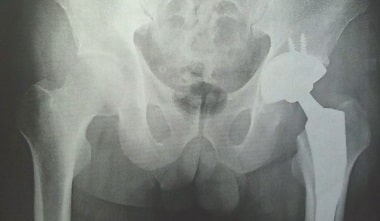

股関節の症状

変形性股関節症

臼蓋形成不全

発育性股関節形成不全

特発性大腿骨頭壊死症

大腿骨頚部骨折

鼠径部痛症候群

骨盤骨折